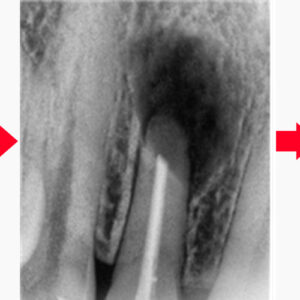

22. 울산남구치과 브릿지에 구멍이 났어요.

울산남구치과 브릿지에 구멍이 났어요.   안녕하세요. 모든 진료에 진심을 다하는 곳, 더플러스치과입니다.   치아를 잃게 되었을 때 이를 대체할 수 있는 방법으로는 임플란트나 브릿지, 틀니 등 다양한 방법이 있습니다.   그중에서도 브릿지는 상실된 치아의 인접한 치아를 삭제한 후 지대치로 사용하여 더보기…